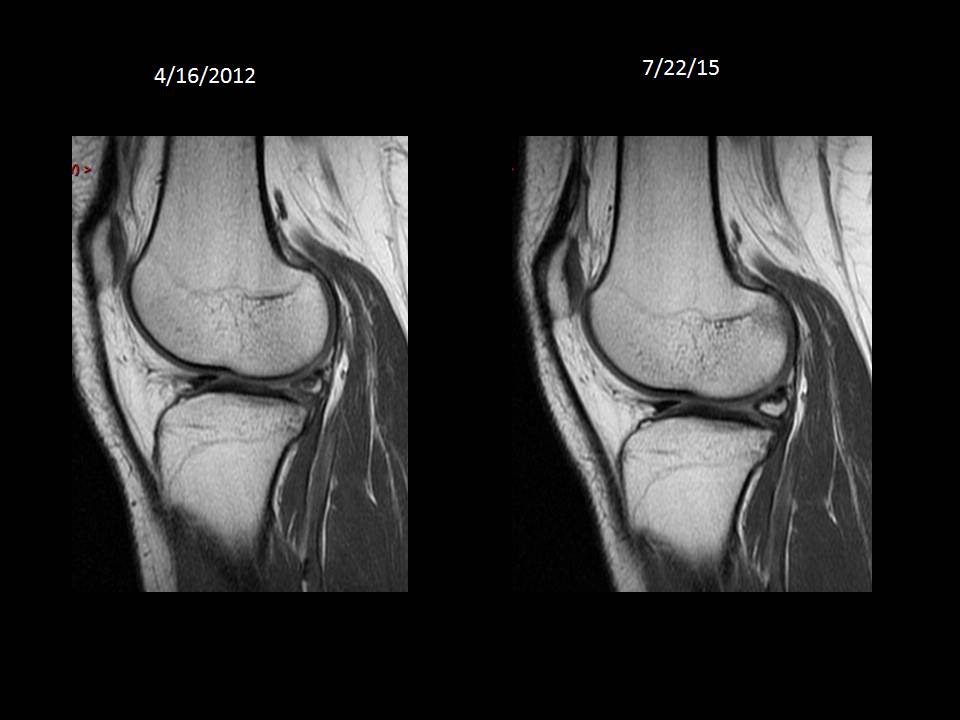

24 y/o F with knee injury in April 2012. Continued pain and instability. No surgery

Comparison images from 2012 and 2015. Meniscal ossicle is maturing and getting larger. Good evidence for post traumatic etiology not congenital.

Meniscle ossicle ( RID10149 )